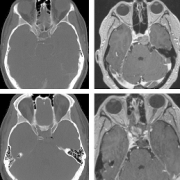

这很有可能是一个斜坡嵴索瘤,现在有332633mm这么大,已经侵袭左侧海绵窦,导致垂体移位、垂体柄歪斜,但手术风险很大,家属要慎重考虑。 几月前,小...

一名37岁的妇女因颈部疼痛和下颅神经功能障碍(声音嘶哑和吞咽困难)被咨询至我科。她先前被诊断出患有(CCJ) 颅颈交界处脊索瘤 ,并且先前在另一家...

法国一位37岁的女士因头痛、视力下降严重,到医院检查,被诊断出颅颈交界处(CCJ) 脊索瘤 。随后在一家比较医院治疗,该院采取了乙状窦后入路手术切除...